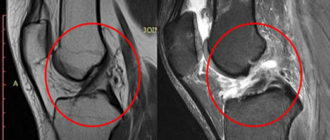

МР-признаки частичного повреждения передней крестообразной связки. Реактивный синовиит. Дегенеративн

Повреждение ПКС — лечение и реабилитация разрыва передней крестообразной связки. Причины. Симптомы. Группы риска